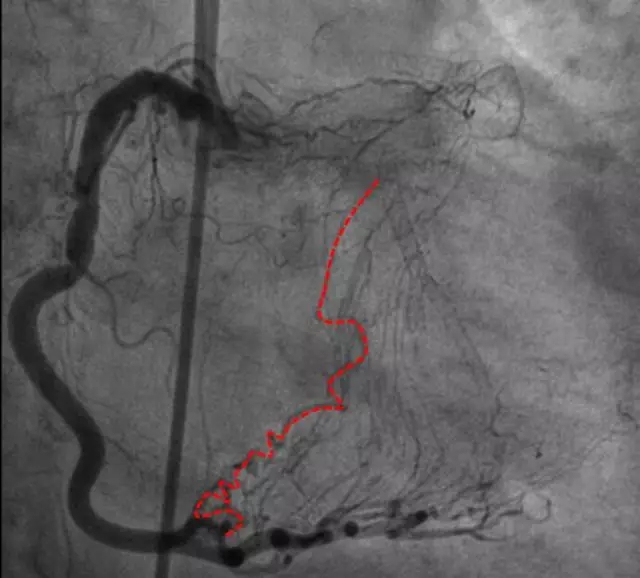

CAG

LM闭塞

RCA粗大,大量左向右侧枝形成

PL-左房支-LCX侧枝

Corsair+SION